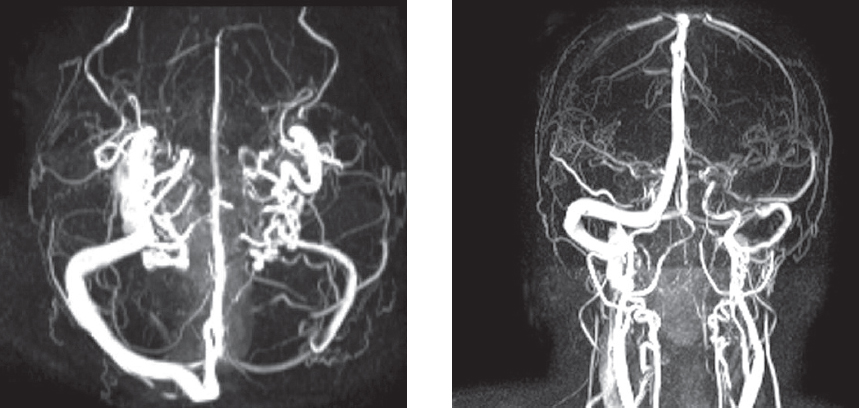

ОСЭП развиваются в 34 % случаев церебральных венозных тромбозов [5], что является «красным флагом» для клинициста. Прогностическими факторами, повышающими риск развития ОСЭП при церебральных венозных тромбозах, являются: внутримозговое кровоизлияние (скорректированное ОШ 4,1; 95 % ДИ 3,0–5,5); отек головного мозга или инфаркт мозга без внутримозгового кровоизлияния (скорректированное ОШ 2,8; 95 % ДИ 2,0–4,0); тромбоз верхнего сагиттального синуса (скорректированное ОШ 2,0; 95 % ДИ 1,5–2,6); очаговый неврологический дефицит (скорректированное ОШ 1,9; 95 % ДИ 1,4–2,6); субарахноидальное кровоизлияние (скорректированное ОШ 1,6; 95 % ДИ 1,1–2,5). Хотя, как показывает клиническая практика, даже при отсутствии очаговой неврологической симптоматики причиной ОСЭП может являться венозный тромбоз, что демонстрирует клинический пример (рис. 2).

Рис. 2. Пациентка М., 51 год. Магнитно-резонансная венография головного мозга: магнитно-резонансные признаки снижения тока крови по левому поперечному синусу, нельзя исключить наличие тромботических масс. Магнитно-резонансная картина асимметрии поперечных, сигмовидных синусов и яремных вен (D > S). Анамнез заболевания. На фоне полного благополучия у пациентки развился билатеральный тонико-клонический приступ, сопровождавшийся прикусом языка, непроизвольным мочеиспусканием. Была госпитализирована в неврологический стационар, диагностирован судорожный эпилептический статус, который был купирован внутривенным введением диазепама и вальпроевой кислоты. В последующем в неврологическом статусе рассеянная неврологическая симптоматика, постприступная спутанность сознания (дезориентация во времени, месте, собственной личности, которая сохранялась в течение одного часа). Были выполнены компьютерная томография и компьютерно-томографическая ангиография головного мозга: компьютерно-томографических данных за наличие патологических образований, участков кровоизлияний, ишемии в веществе головного мозга, артериовенозных мальформаций, аневризматических расширений сосудов головного мозга не выявлено. С учетом данных анамнеза и клинической картины, повышения уровня D-димера в плазме крови до 3300 нг/мл, проводился дальнейший диагностический поиск. По результатам магнитно-резонансной венографии диагностирован тромбоз венозного синуса без формирования инфаркта головного мозга